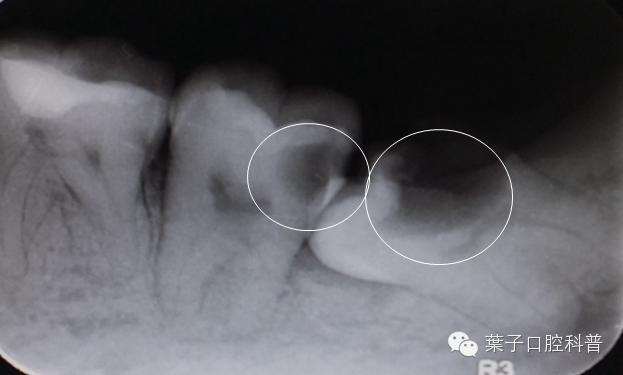

智齿以及前面的第二磨牙龋坏